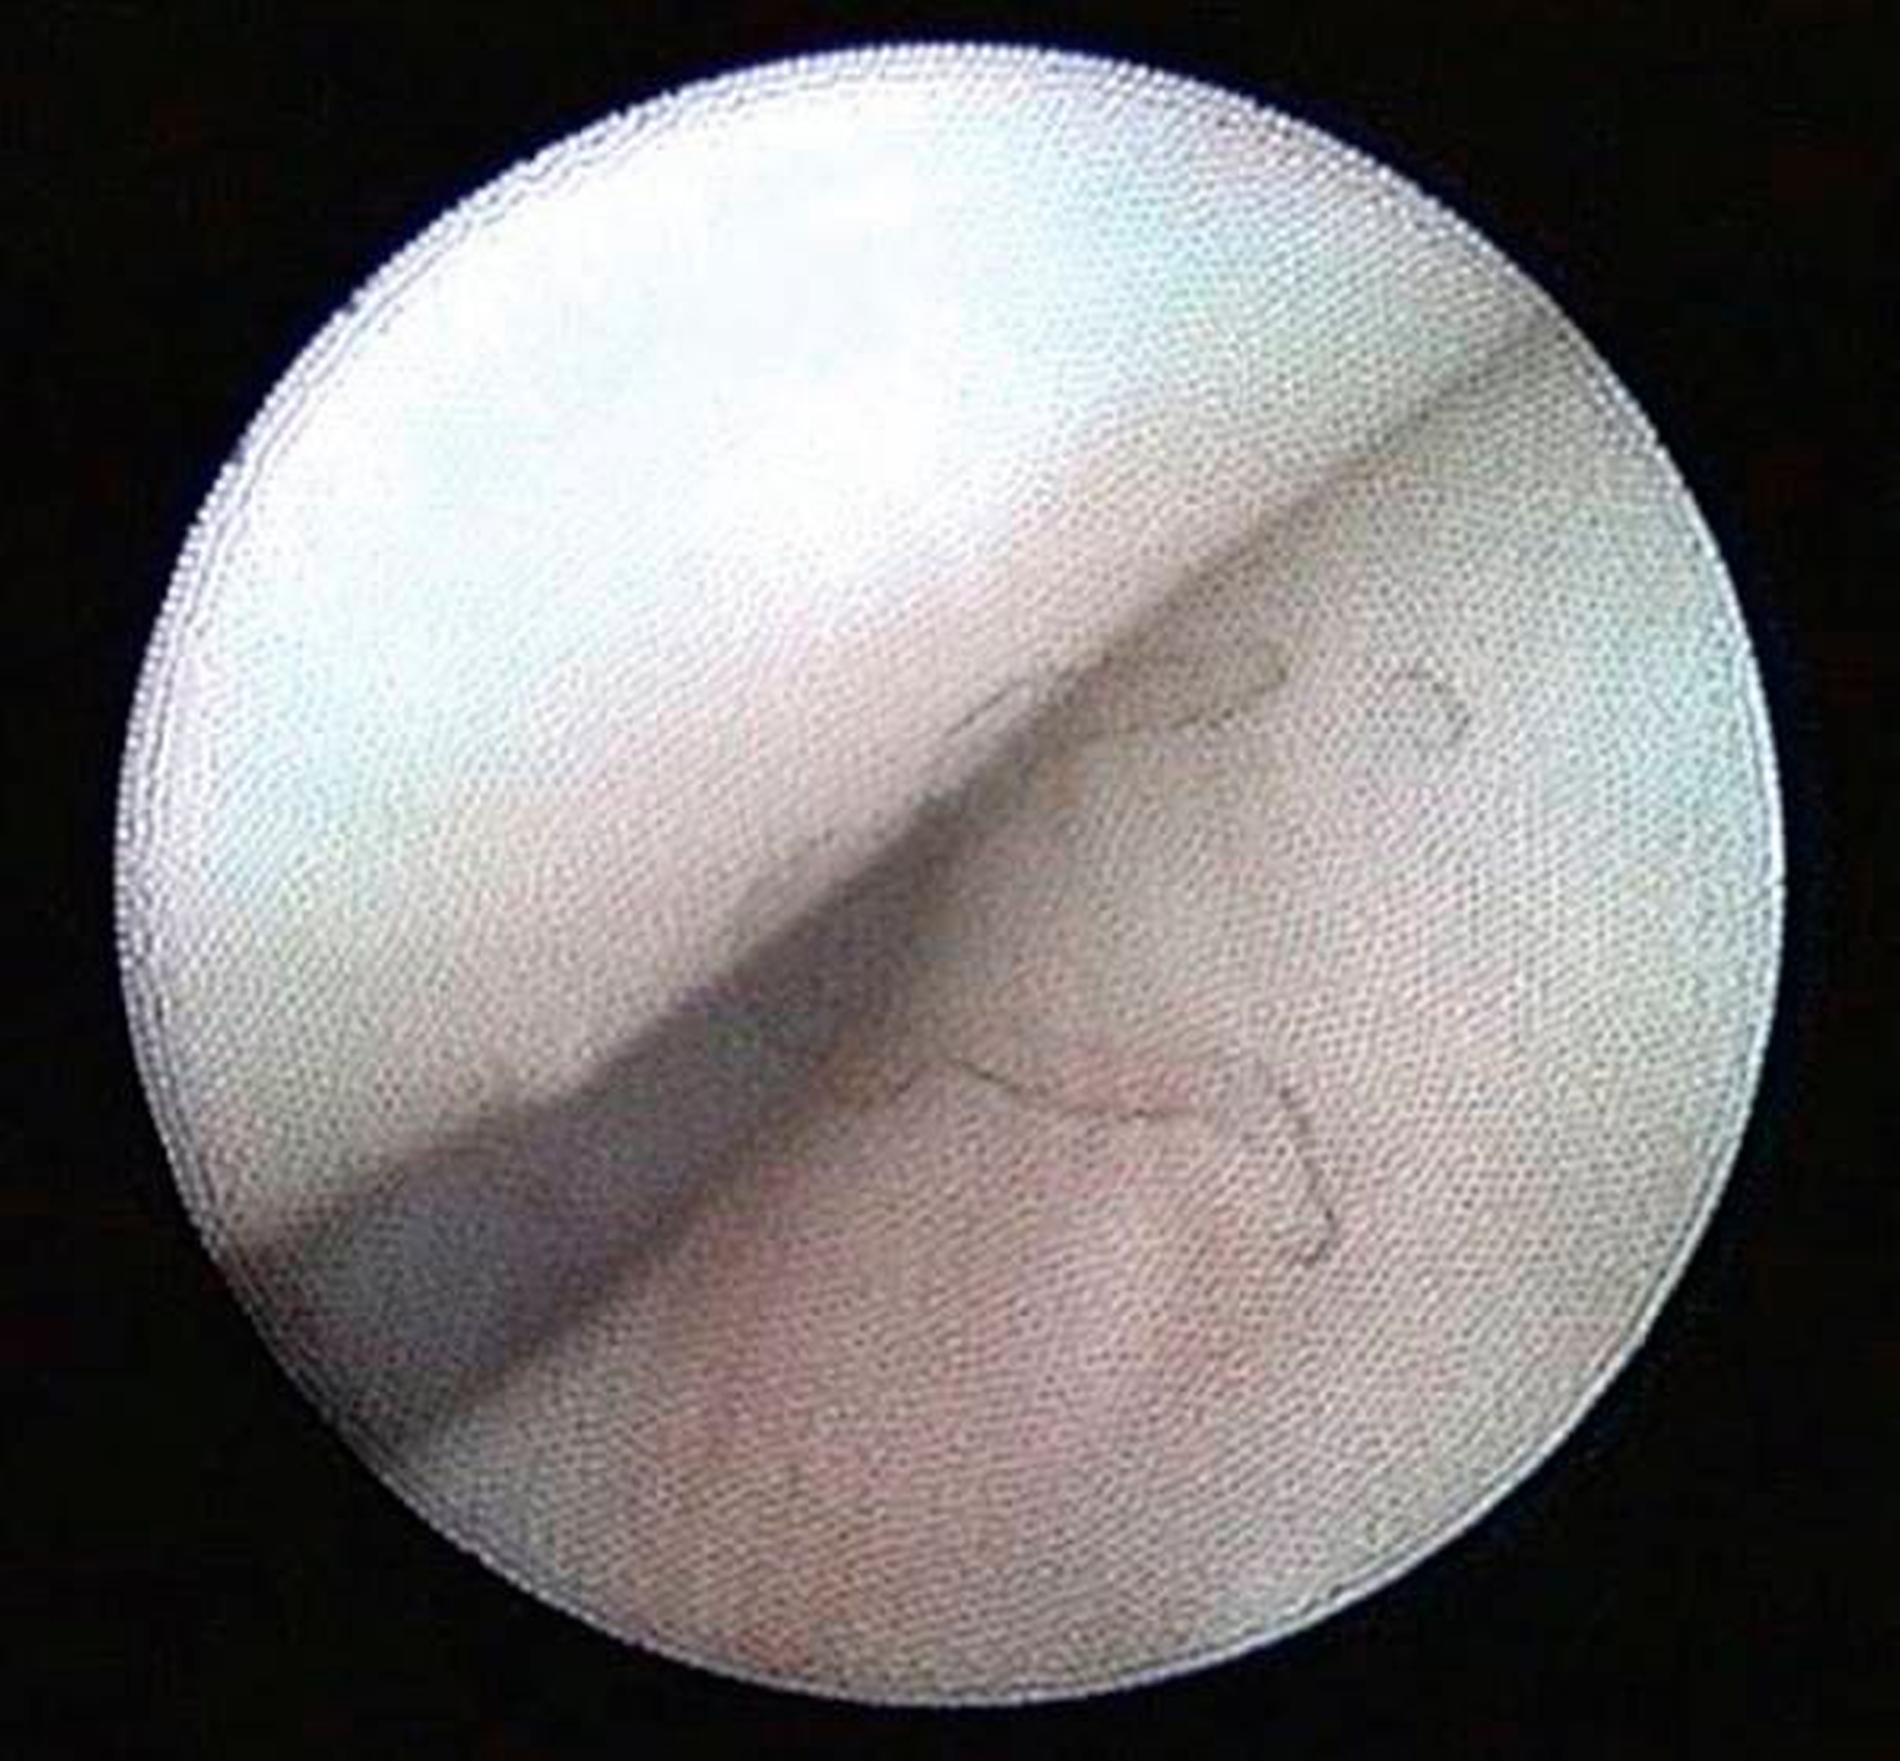

Arthroskopisch existieren verschiedene Klassifikationen der Synoviitis, die im Wesentlichen das Ausmaß der beobachteten Gefäßproliferation und Hyperämie berücksichtigt (Abbildungen 4 bis 6) [Mc Cain et al., 1989; Gynther et al.,1994].

Selbst durch die MRT können bestimmte frühe Entzündungszustände der Kiefergelenke (beispielsweise die Synoviitis) bei fehlendem Gelenkerguss nicht direkt erfasst werden (radiologisch okkulte Kiefergelenksentzündungen). In der Praxis stellen symptomatische, aber radiologisch okkulte Entzündungszustände insbesondere im Fall einer Therapieresistenz auf konservative Therapiemaßnahmen (wie Schienen- und Physiotherapie) eine besondere Herausforderung dar, weil hier die Gefahr von Fehldiagnosen besonders groß ist (Abbildungen 4 bis 6).

Zur Planung eines arthroskopischen Eingriffs am Kiefergelenk sollte ein möglichst aktuelles MRT der Kiefergelenke vorliegen, sofern hierfür keine Kontraindikationen bestehen. Dabei ist zu beachten, dass radioogisch diagnostizierte Pathologien durch die MRT nicht zwingend voraussetzend für eine Kiefergelenksarthroskopie sind. Bei Patienten mit symptomatischen Kiefergelenkschmerzen, aber radiologisch okkulten Kiefergelenksentzündungen ist die Kiefergelenksarthroskopie bislang immer noch das einzig relevante Verfahren zur Sicherung der Diagnose (Abbildungen 4 bis 6).